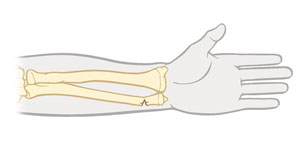

Fractura abierta

El hueso atraviesa la piel. (Una fractura que no atraviesa la piel se denomina fractura cerrada). También recibe el nombre de fractura expuesta.